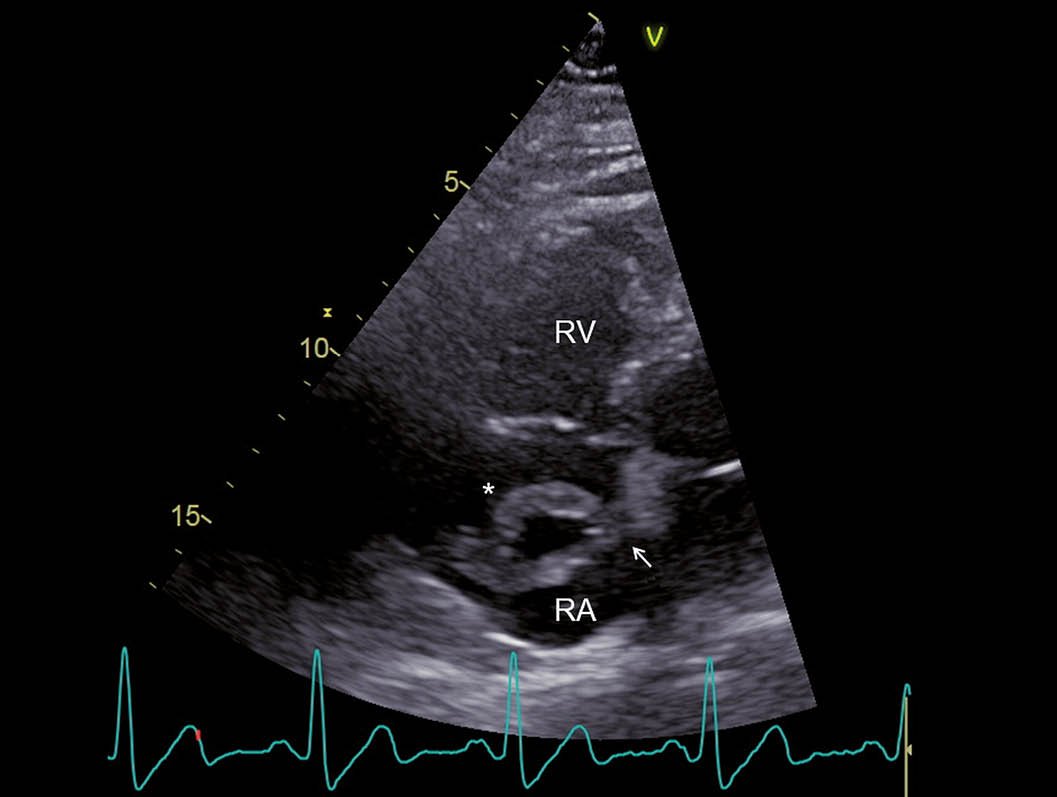

Ein 52-jähriger Patient musste sich wegen eines bronchialen Plattenepithelkarzinoms einer linksseitigen Unterlappenresektion unterziehen. Einige Tage postoperativ klagte der Patient plötzlich über starke Schmerzen im rechten Bein. Ferner bestand eine zunehmende Dyspnoe. Es zeigte sich im ischämischen rechten Bein ein ausgedehnter arterieller Gefässverschluss, welcher durch einen komplexen notfallmässigen Eingriff mit Thrombendarterektomie und Thrombektomie behandelt werden konnte. Die weiteren Abklärungen ergaben den Nachweis von tiefen Beinvenenthrombosen und von ausgedehnten beidseitigen Lungenembolien. Im Labor zeigte sich eine Thrombozytopenie und es wurde die Diagnose einer heparininduzierten Thrombozytopenie Typ II gestellt. Entsprechend wurde die Antikoagulation auf Bivalirudin umgestellt. Im Rahmen der Untersuchungen wurde eine transthorakale Echokardiographie durchgeführt. Hierbei zeigte sich ein dilatierter, exzentrisch hypertropher rechter Ventrikel (Abb. 1) und es fanden sich Zeichen einer ausgeprägten pulmonal-arteriellen Hypertonie (Abb. 2). Im rechten Vorhof zeigte sich ein grosser Thrombus, welcher am interatrialen Septum adhärent zu sein schien (Abb. 3). Ein Teil des Thrombus prolabierte durch die Trikuspidalklappe in den rechten Ventrikel (Abb. 4). Es wurde interdisziplinär entschieden, den grossen ‘Thrombus-in-Transit’ nach Stabilisierung des Patienten operativ zu entfernen. Die intraoperativ durchgeführte transösophageale Echokardiographie liess erkennen, dass der Thrombus nun durch ein persistierendes Foramen ovale (PFO) in den linken Vorhof prolabierte (Abb. 5). Bei der operativen Entfernung zeigte sich, dass der Thrombus in Fäden der Valvula Eustachii verfangen war (Abb. 6), was eine weitere Migration des Thrombus verhinderte. Der Anteil, welcher durch das PFO prolabierte, liess sich ohne Widerstand herausnehmen. Nach Entfernung des Thrombus wurde das Foramen ovale verschlossen. Die Operation verlief erfolgreich. Nach initial protrahiertem Verlauf erholte sich der Patient sehr gut und es zeigte sich eine deutliche Regredienz der pulmonal-arteriellen Hypertonie. Die Antikoagulation mit Bivalirudin wurde in der Folge auf Marcoumar umgestellt; es kam zu keinen weiteren thromboembolischen Komplikationen.

Abb. 3: RV-modifizierter apikaler Vierkammerblick Im rechten Atrium zeigt sich ein grosser, zweischenkliger Thrombus (*), welcher am interatrialen Septum adhärent zu sein scheint (Pfeil). RV = rechter Ventrikel und RA = rechtes Atrium.

Abb. 4: RV-modifizierter apikaler Vierkammerblick Erneute Darstellung des grossen rechtsatrialen Thrombus (*), wobei in diesem Bild der grössere der beiden Schenkel durch die Trikuspidalklappe in den rechten Ventrikel prolabiert (Pfeil). RV = rechter Ventrikel und RA = rechtes Atrium.